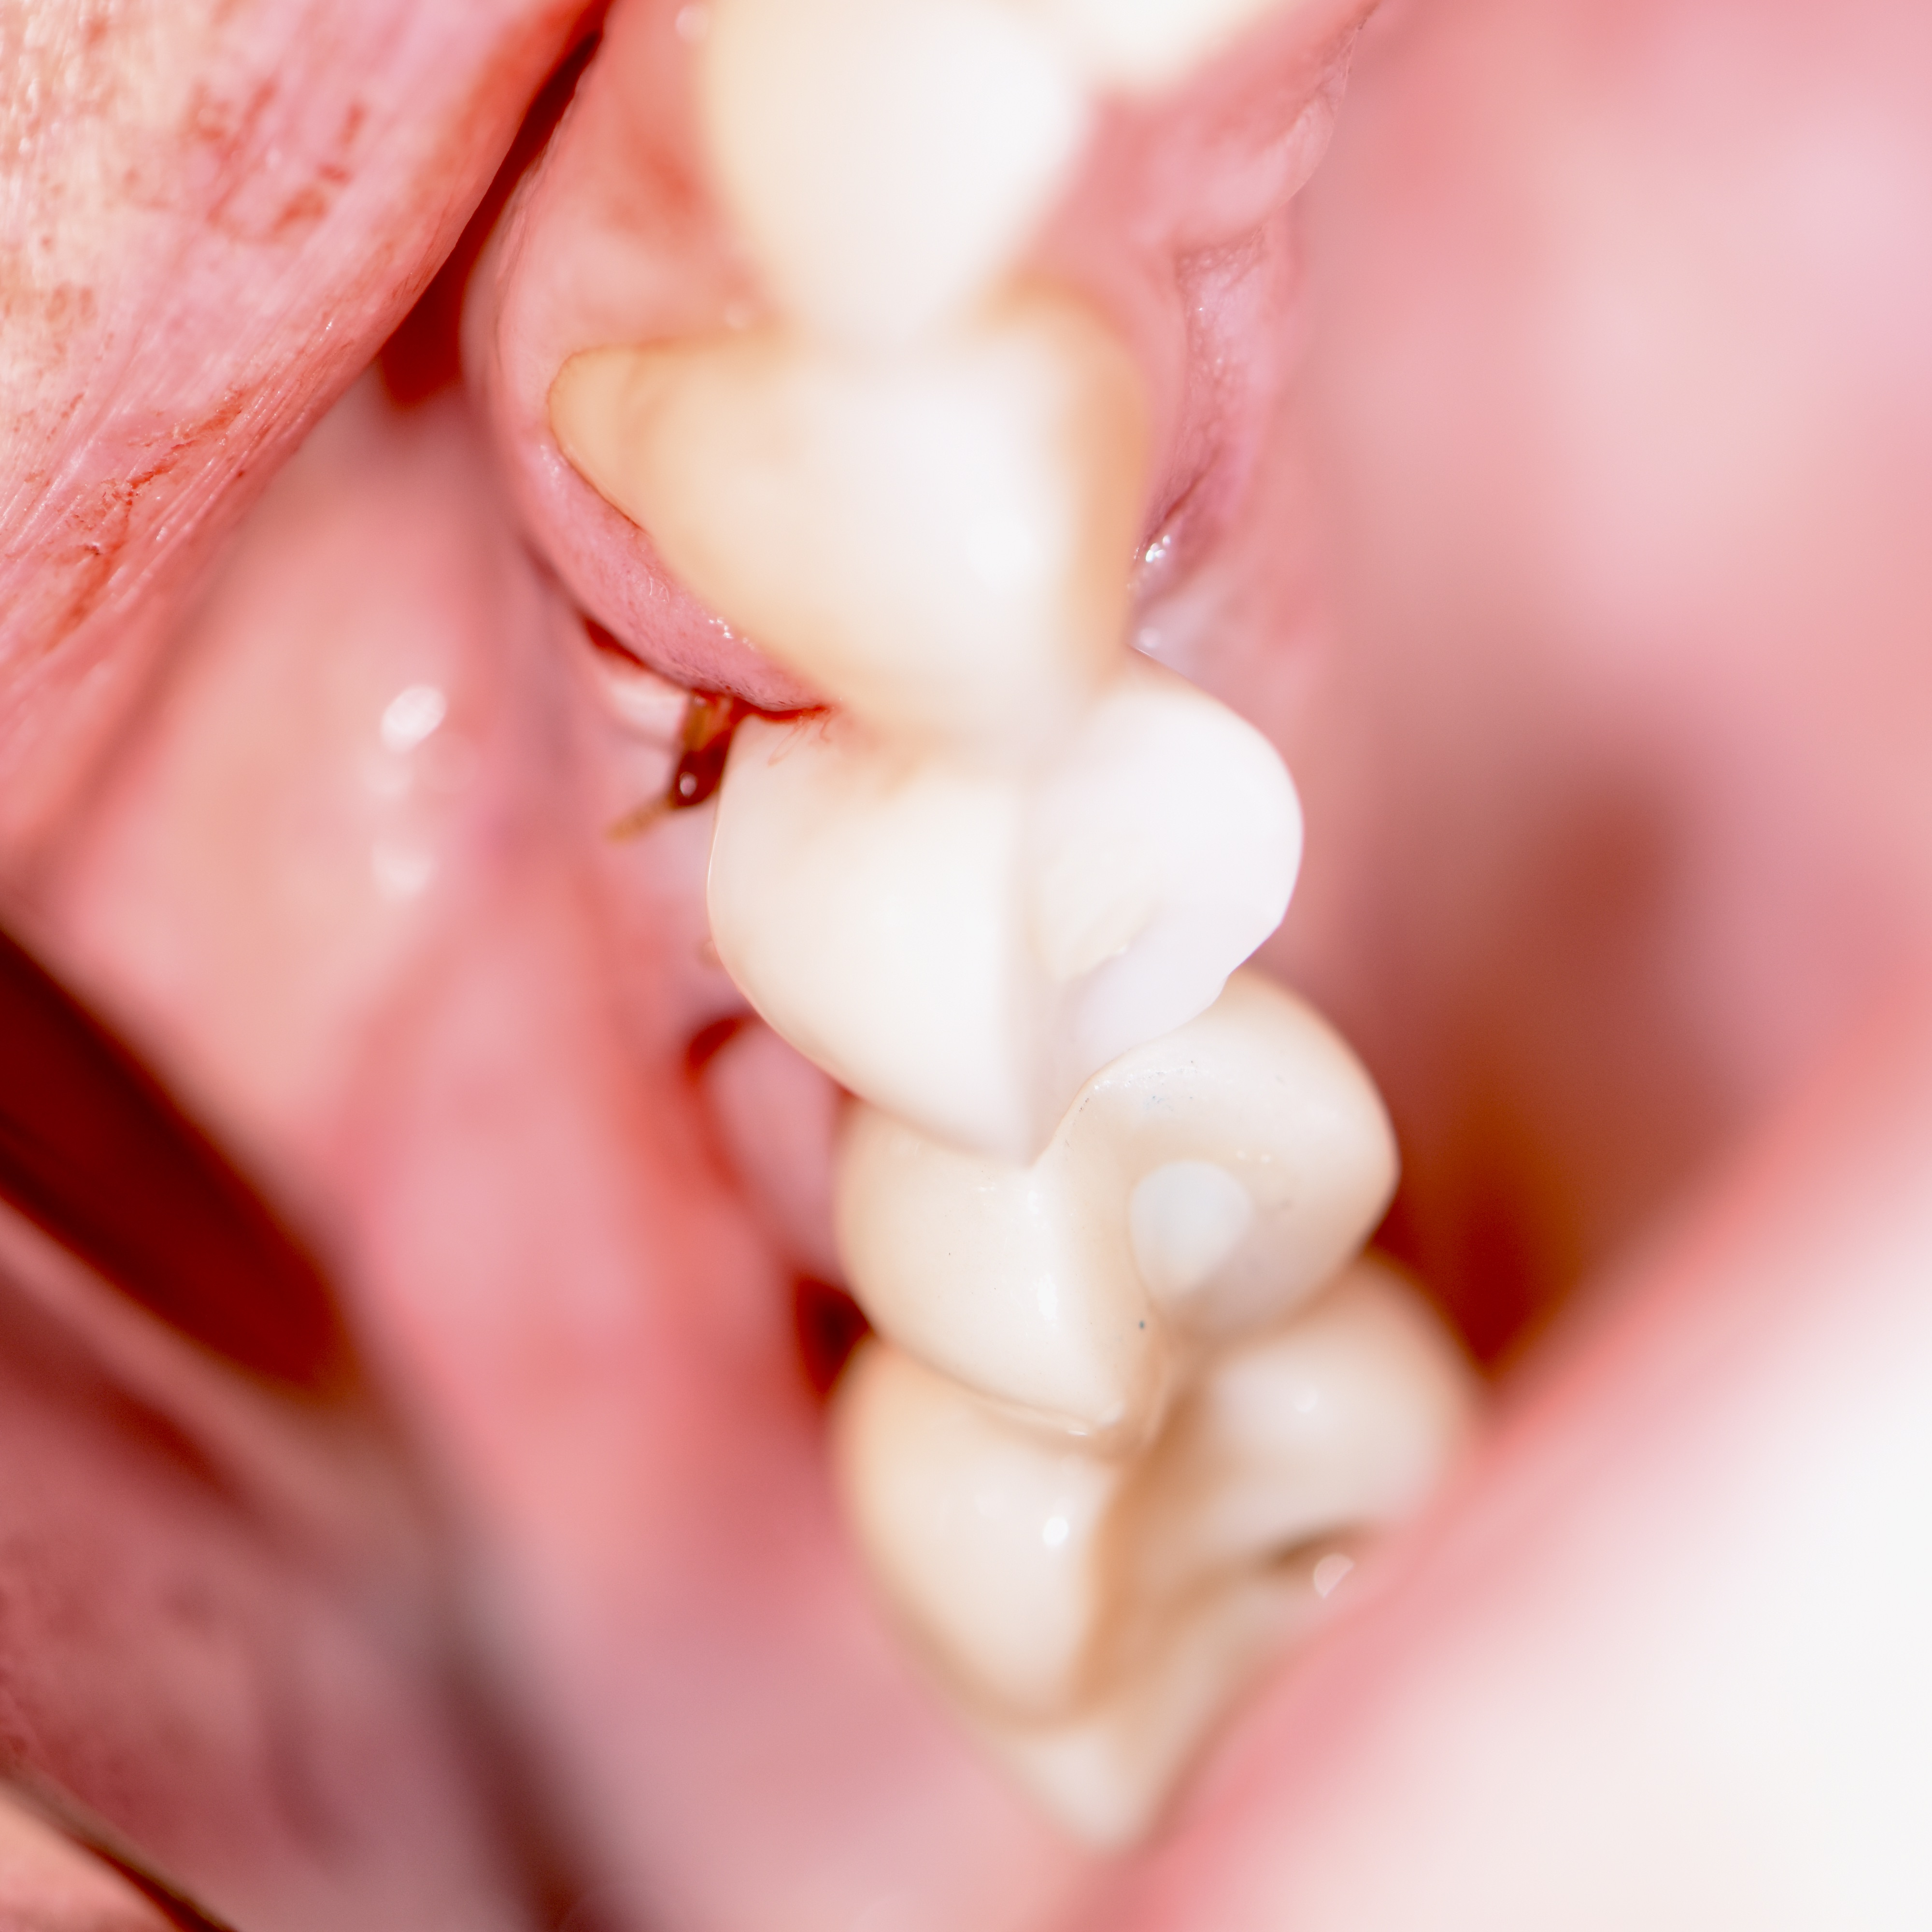

Broken Filling and Cavity Repair